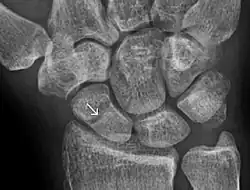

An X-ray showing a fracture through the waist of the scaphoid

Fracture of the tubercle of the scaphoid bone of the wrist